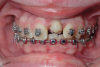

Fig 4. A 15-year postoperative photograph of the patient in Fig 3 illustrates the significant infraocclusion of the implants compared to the natural teeth. Also, note the blue tissue discoloration over implants Nos. 7 and 11.

Fig 3. Implants were placed in a 20-year-old female patient in the Nos. 7 and 11 sites with a pontic replacing No. 10.

A third risk of using an implant to replace a missing lateral incisor is the continued vertical growth of the alveolar bone and eruption of the teeth adjacent to the implant.9,10 Traditionally, it has been taught that an implant can be safely placed when alveolar bone growth is confirmed complete with serial radiographs. However, numerous studies call that rule into question.11-16 Bernard et al evaluated vertical changes in teeth adjacent to implants in a young group of patients (15.5 to 21 years) and in a mature group (40 to 55 years), over a mean time of 4.2 years.17 In the young group, infraocclusion of the implant crowns ranged from 0.1 mm to 1.65 mm, while in the mature group the infraocclusion of the implant crowns ranged from 0.12 mm to 1.86 mm. An example of infraocclusion that occurred in a young implant patient over time is depicted in Figure 3 and Figure 4. Based on classic literature as cited here, it seems prudent to delay the placement of implants in high-risk areas, such as the maxillary lateral incisor region, for as long as possible or perhaps avoid it altogether.